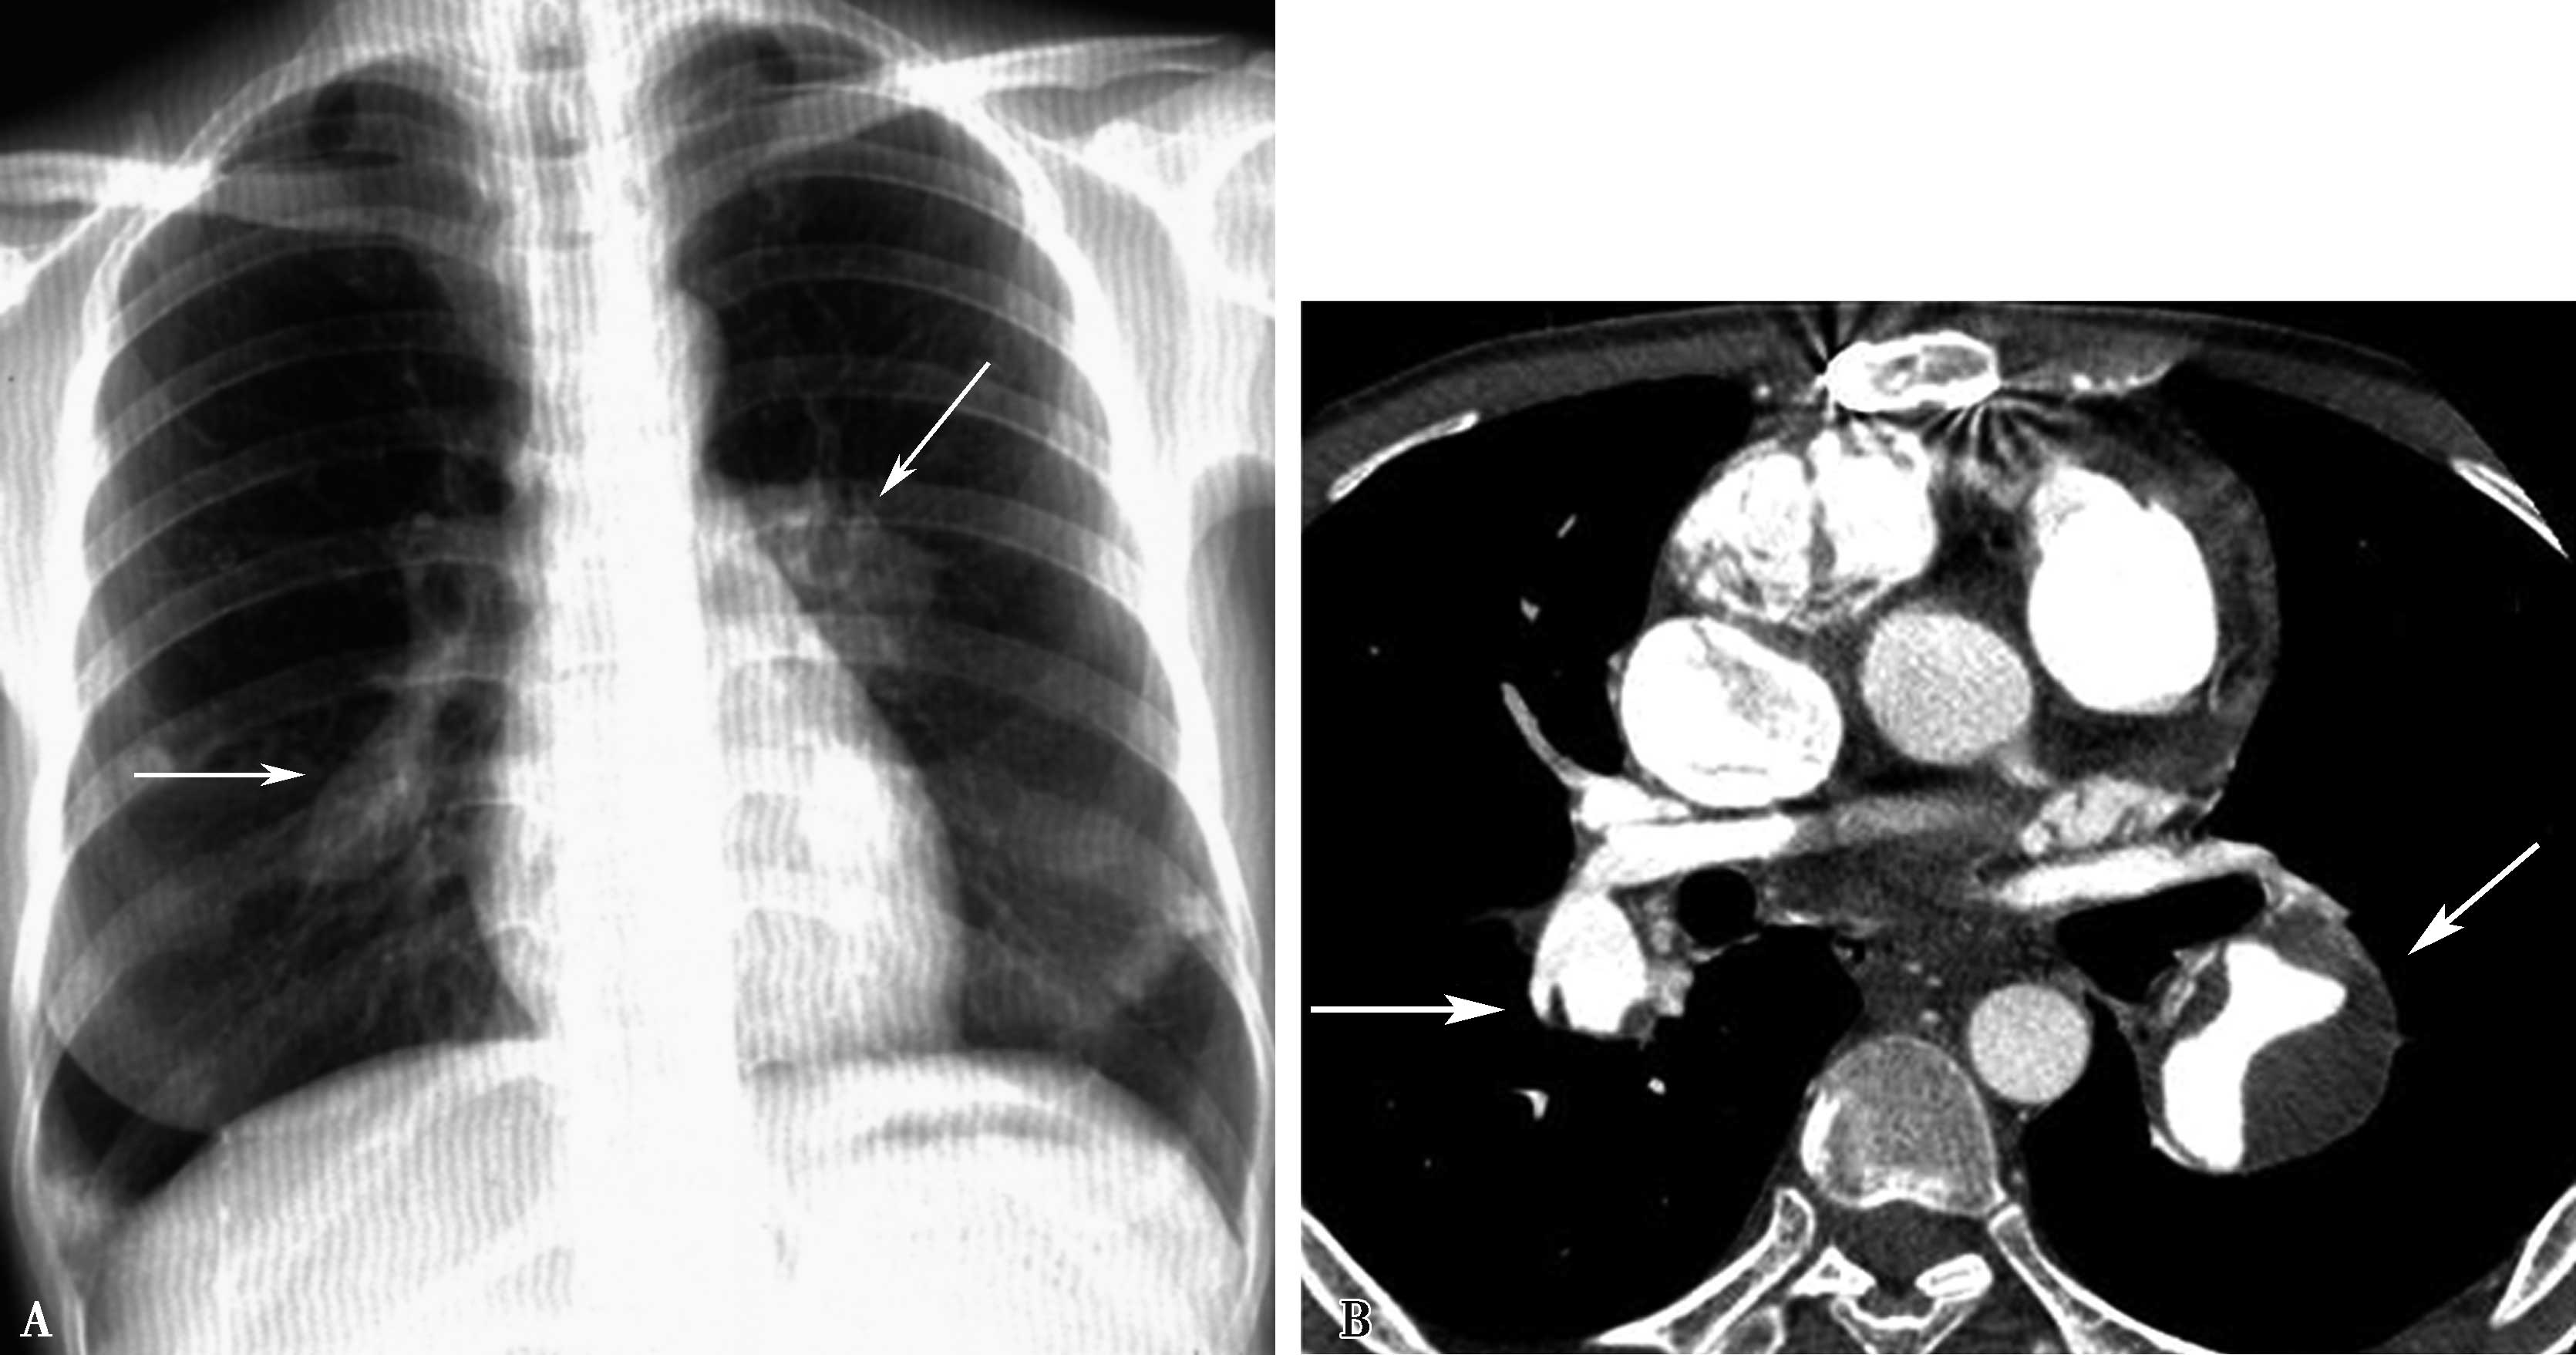

图7-2-8 女婴,3个月,气促,发绀;X线胸片示右下肺实变不张(A↑);右心增大。CTA:右下肺静脉闭锁(BC↑),右肺下叶实变不张,右心房室增大。肺动脉高压